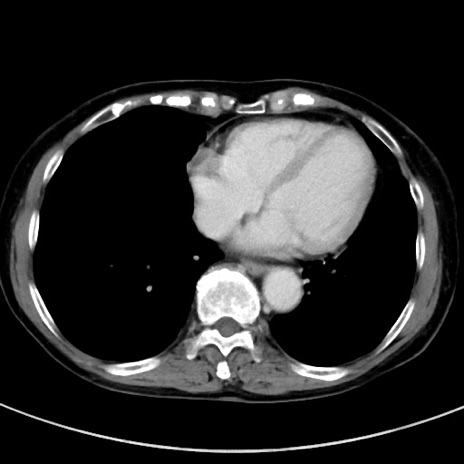

症例23(横断像)

【症例】70歳代女性

【主訴】下腹部痛・嘔吐

【現病歴】2日前より腹痛あり。昨日嘔吐あり。症状改善しないため来院。

【既往歴】胃GISTに対して胃部分切除後。

【身体所見】BT 37.1℃、BP 128/77mmHg、腹部:平坦・軟、下腹部に圧痛あり。

【データ】WBC 10200、CRP 0.31